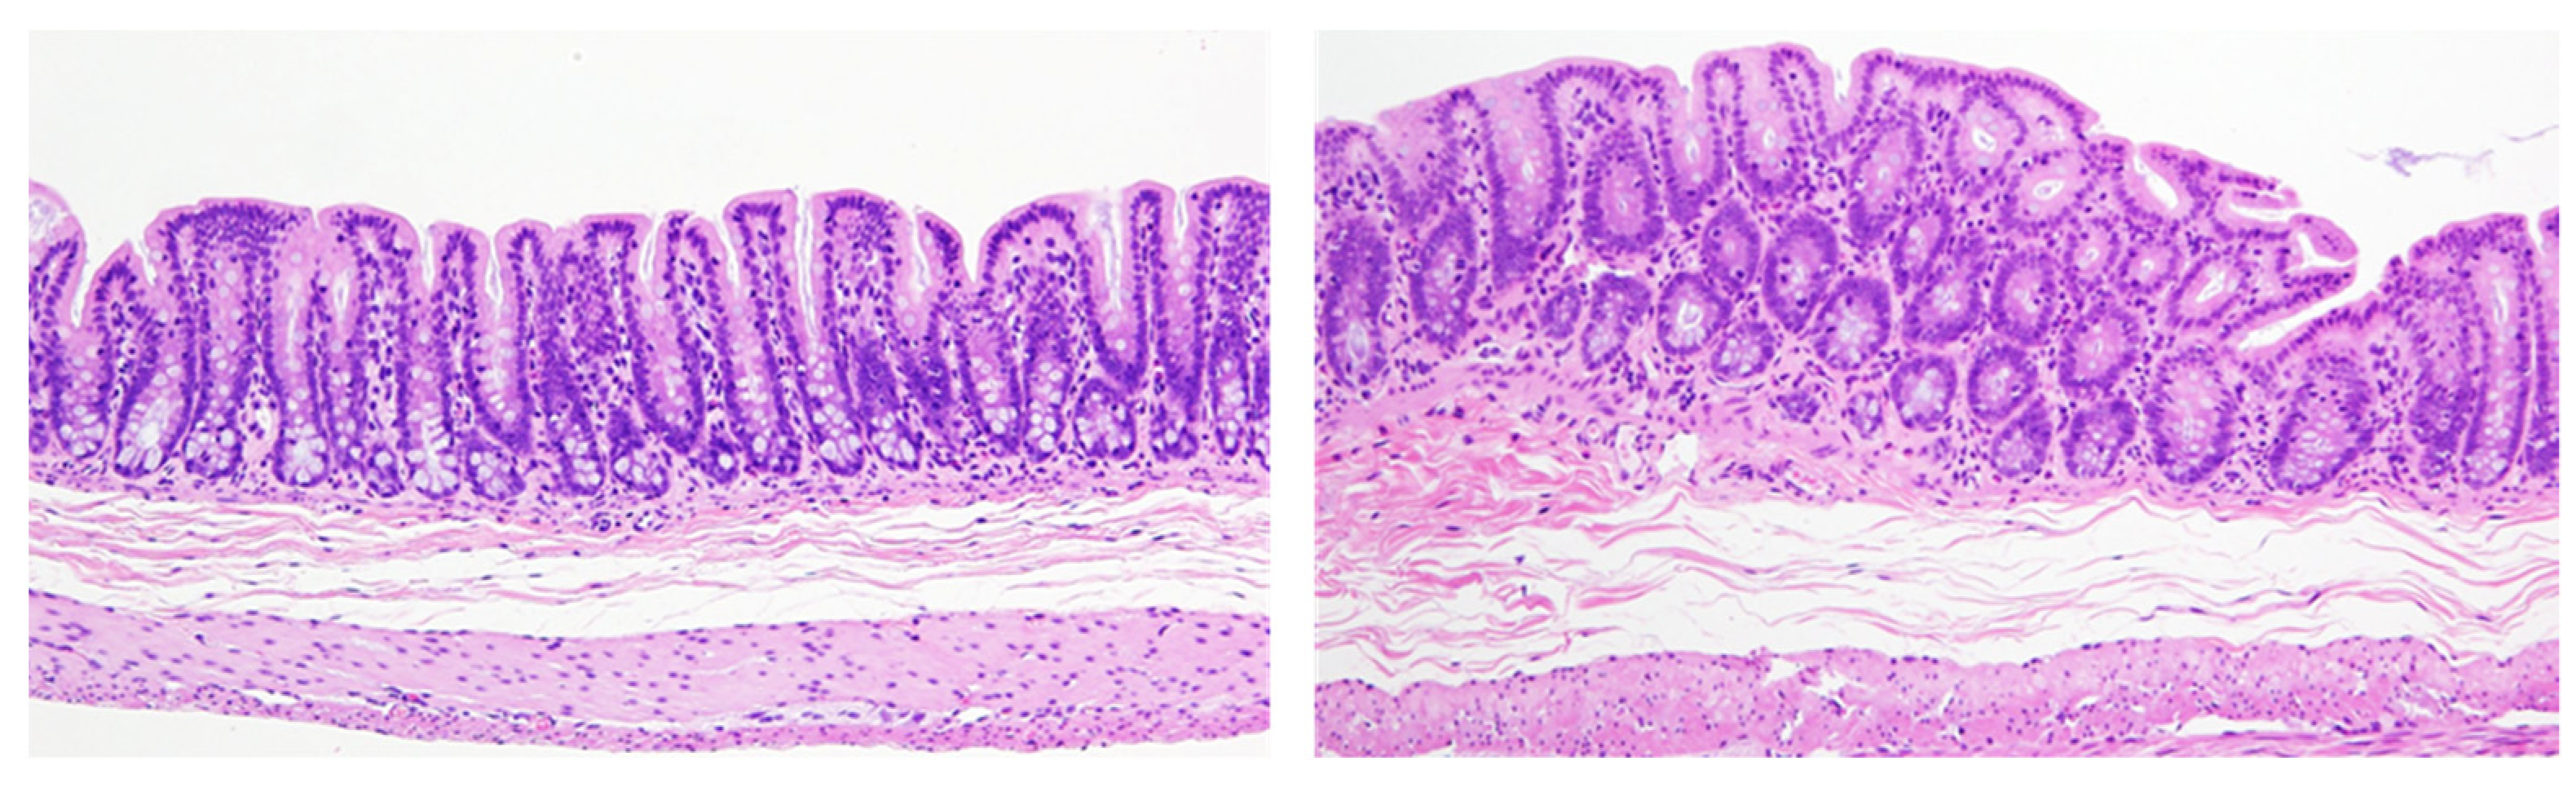

- If there is a difference in cell proliferation across the organ, it would be necessary to evaluate the fields evenly to reflect the whole organ. For example, the epithelial cells in the gastrointestinal tract and urinary bladder have certain proliferative zones consisting of immature cells located mostly in the basal layer of the urothelium or in the crypts of the intestine, but middle height in the mucosal glands in the stomach. A bias may occur in the ratio between the different layers depending on how the organ is cut, so care must be taken to make the sectioning representative of the normal distribution of target cells (Figure 5). To avoid this bias, a greater number of cells should be evaluated compared to more homogenous tissues.